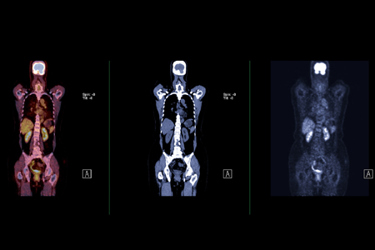

“In the case of our first product that received FDA approval in 2020 — the diagnostic agent copper-64, or Detectnet — we knew how to develop the study,” said Delpassand. “We knew how to perform the clinical trials. But for the commercial launch of the drug, we thought we would need to partner with a big company that has done this many times with other drugs.”

Curium already had “boots on the ground” selling Octreoscan, a neuroendocrine cancer diagnostic, said Delpassand. Licensing RadioMedix’s Detectnet diagnostic to Curium helped to make the commercial launch a success, leading to Detectnet capturing “more than 70% of the market,” despite the availability of a competing product approved at an earlier date. “We have a majority of the market because of Detectnet’s ease of use, and because it’s centrally manufactured and available throughout the country,” said Delpbassand. “Wherever there is a PET scanner, Curium can ship the product and patients can benefit.”